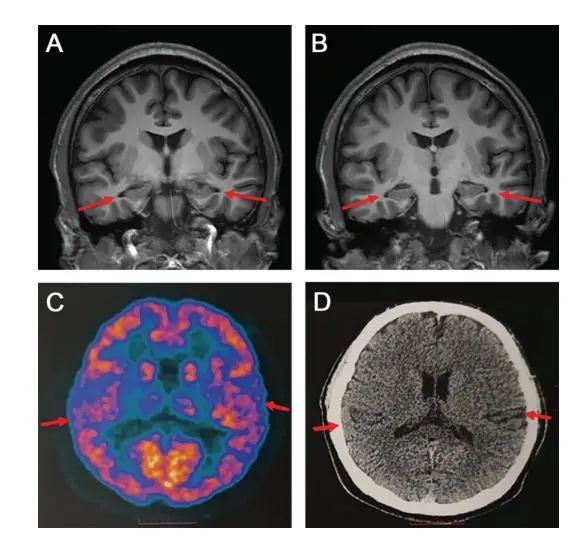

论文中表示,医院为患者做了多种检查,包括当前用于诊断阿尔兹海默病的最权威手段——脑脊液指标检测和PET扫描,患者还接受了多种量表测试。扫描影像等显示,患者存在轻度的脑萎缩等症状,部分脑脊液指标也存在异常,最终患者被临床诊断为阿尔兹海默症患者。